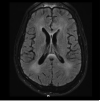

Neurological involvement in HIV is often associated with cognitive impairment. Although severe and progressive neurocognitive impairment has become rare in HIV clinics in the era of potent antiretroviral therapy, most patients with HIV worldwide have poor outcomes on formal neurocognitive tests. In this Review, we describe the manifestations of HIV-associated neurocognitive disorder in the era of effective HIV therapy, outline diagnosis and treatment recommendations, and explore the research questions that remain. Although comorbid disorders, such as hepatitis C infection or epilepsy, might cause some impairment, their prevalence is insufficient to explain the frequency with which it is encountered. HIV disease markers, such as viral load and CD4 cell counts, are not strongly associated with ongoing impairment on treatment, whereas cardiovascular disease markers and inflammatory markers are. New cerebrospinal fluid and neuroimaging biomarkers are needed to detect and follow impairment. Ongoing research efforts to optimise HIV therapy within the CNS, and potentially to intervene in downstream mechanisms of neurotoxicity, remain important avenues for future investigation. Ultimately, the full control of virus in the brain is a necessary step in the goal of HIV eradication.